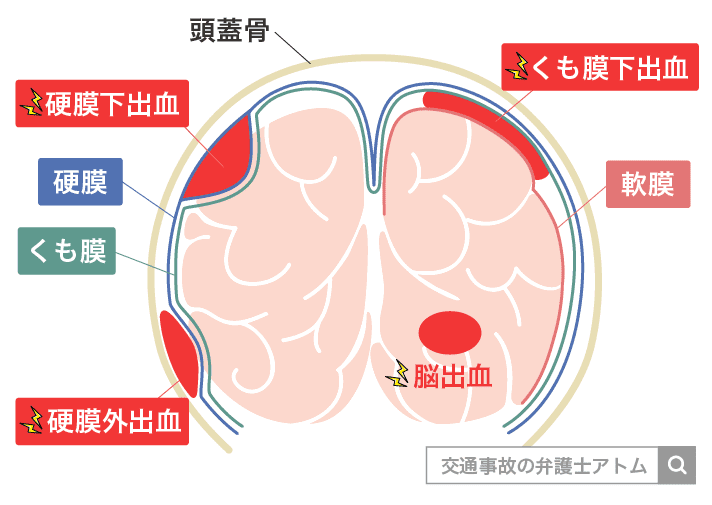

慢性硬膜下血腫

慢性硬膜下血腫 対象疾患 医療関係者へ 近畿大学医学部 脳神経外科

外傷性硬膜下血腫の後遺症 症状は手術で治る 予後不良の後遺障害慰謝料はいくら アトム法律事務所弁護士法人

慢性硬膜下血腫 対応疾患 流山中央病院 脳神経外科ホームページです 日本脳神経血管内治療学会研修施設 認定病院 脳動脈瘤 クモ膜下 出血 脳出血 脳梗塞などの血管障害だけでなく 脳動静脈奇形や硬膜動静脈瘻といった 珍しい疾患もカバーしています

慢性硬膜下血腫とは 症状 手術法と費用 治療法など 介護のほんね